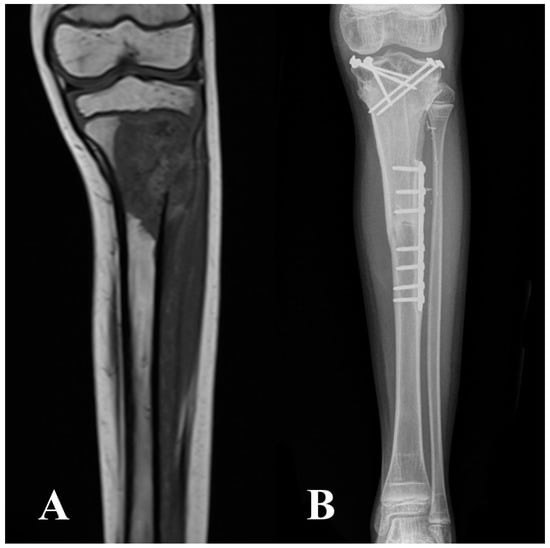

2.2. Surgical Technique, Aftercare, and Cancer Treatment

| Intercalary | 77 (10) | 58 (15) |

| Intraepiphyseal | 23 (3) | 42 (11) |

| Single bridging plate | 77 (10) | 35 (9) |